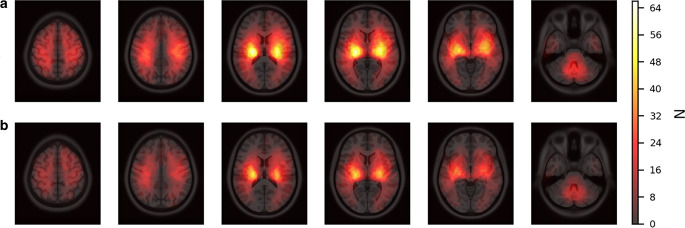

Methods: Our retrospective analysis included 322 ICH patients. We defined myocardial injury as an elevation of hs-cTnT above the 99th percentile (i.e. 14 ng/L). Acute myocardial injury was defined as either a changing pattern of > 50% within 24 h or an excessive elevation of initial hs-cTnT (> 52 ng/L). 3D brain scans were assessed for ICH visually and quantitatively by a deep learning algorithm. Multiple regression models and Voxel-based Lesion-Symptom Mapping (VLSM) were applied.

Results: 63.0% (203/322) of patients presented with myocardial injury, which was associated with more severe strokes and worse outcomes during the in-hospital phase (P < 0.01). Acute myocardial injury occurred in 24.5% (79/322) of patients. The only imaging finding associated with acute myocardial injury was midline shift (69.8% vs. 44.6% for normal or stable hs-cTnT, P < 0.01), which also independently predicted it (odds ratio 3.29, confidence interval 1.38-7.87, P < 0.01). In contrast, VLSM did not identify any specific brain region significantly associated with acute myocardial injury. Acute myocardial injury did not correlate with preexisting cardiac diseases; however, the frequency of adverse cardiac events was higher in the acute myocardial injury group (11.4% vs. 4.1% in patients with normal and/or stable patterns of hs-cTnT, P < 0.05).